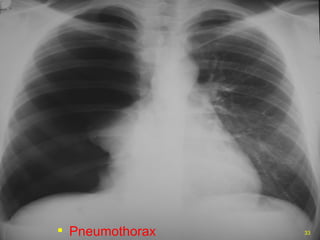

PNEUMOTHORAX

TENSION PNEUMOTHORAX

• #33 Air in the pleural space separates the visceral and parietal pleura. This limits effective ventilation of the lung.

• #35 Here air has built up under pressure in the pleural space and collapsed the lung severely compromising ventilation. The pressure builds due to a ball valve type leak of air into the pleural space with air going into the space on each inspiration.